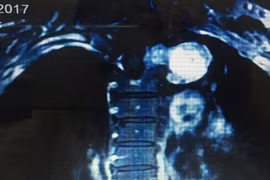

Ngày 21-8, Bệnh viện K Trung ương cho biết, các bác sĩ của bệnh viện vừa phẫu thuật cắt thành công khối u khổng lồ ở tủy sống và lồng ngực rất hiếm gặp cho một nữ bệnh nhân 61 tuổi ở Quảng Ninh.